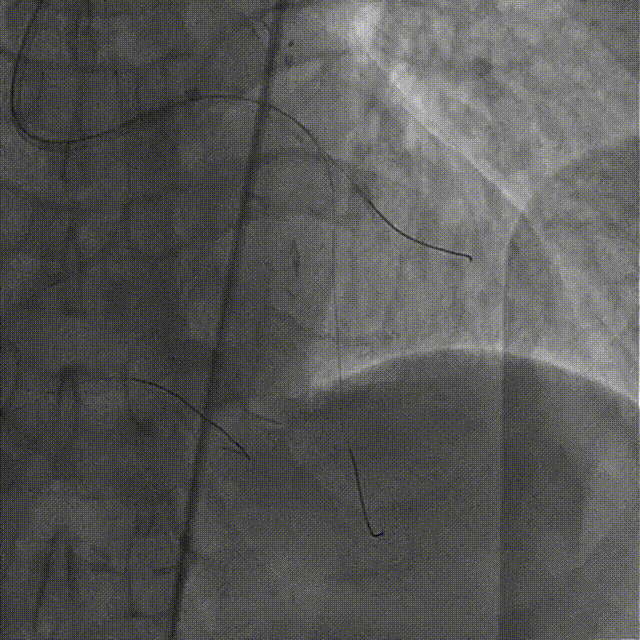

造影示支架定位良好,D1开口受压90%狭窄,交换一根SION导丝穿支架网眼至D1远段,用Pinoeer1.5mm x 15mm、Pinoeer 2.0mm x 15mm球囊至D1开口处扩张。

FOXTROT NC 2.5mm x 15mm、FOXTROT 3.0 mm x 15mm后扩球囊后扩球囊至支架内后扩,以实现支架的充分贴壁,并对LAD远段进行球囊扩张,造影显示TIMI血流III级。

术后行IVUS检查示:支架定位贴壁扩张良好,LAD开口MSA:7.43mm2。